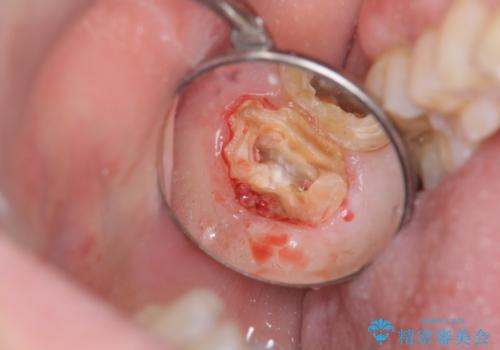

- 銀歯をやりかえたいが他院で抜歯と言われセカンドオピニオンで来院。適合の悪い被せ物が入っており、まずは古い材料、虫歯をとり保存可能か確かめる必要があり、拡大鏡下で全て取り除いたら歯質が歯茎の中まで虫歯がありました。このまま無理やり型取りをして被せ物を作っても不適合な被せ物が入る可能性が高いため歯茎を切り取る手術(ディスタルウェッジ)を行いました。そして再根管治療を行いゴールドの被せ物で治療を行いました。